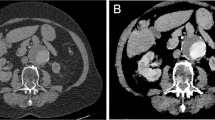

Qualitative diagnostic quality scores in normal aortic segments were 0.9 ± 0.3 and 2.7 ± 0.6 on TNC and dark-blood images, respectively (p < 0.001). Aortic vessel wall conspicuity scores were 0.7 ± 0.5 and 1.8 ± 0.3 on TNC and dark-blood images, respectively (p < 0.001). Similarly, in aortic segments with IMH, the diagnostic quality scores were 1.7 ± 0.5 and 2.4 ± 0.6 on TNC and dark-blood images, respectively (p < 0.001). Aortic vessel wall conspicuity scores were 0.7 ± 0.7 and 1.8 ± 0.3 on TNC and dark-blood images, respectively (p < 0.001). The intra-rater agreement was substantial (weighted kappa = 0.77 and 0.71 for diagnostic quality and aortic wall conspicuity, respectively). The interrater agreement was substantial (weighted kappa = 0.74 and 0.66 for diagnostic quality and aortic wall conspicuity, respectively). Average qualitative diagnostic quality scores, including both IMH patients and control subjects, are shown in Fig. 2, and average vessel wall conspicuity scores, including both IMH patients and control subjects, are shown in Fig. 3. Finally, dark-blood images did not lead to false-positives or negatives for IMH identification.

Qualitative analysis of vessel conspicuity on a 3-point Likert scale (2 = circumscribed margin, 1 = indistinct margin, 0 = obscured margin). Bar graph represents mean scores of observers one and two. Overall conspicuity is the average of outer and inner wall conspicuity. Error bars represent standard deviation

In the quantitative analysis (Fig. 4), normal aortic segment CNRs between the vessel wall and lumen were 0.3 ± 0.2 and 2.8 ± 0.9 on TNC and dark-blood images, respectively (p < 0.001); CNRs between the vessel wall and the periaortic fat were 9.5 ± 2.6 and 2.6 ± 1.2 on TNC and dark-blood images, respectively (p < 0.001). Similarly, in aortic segments with IMH, CNRs between the vessel wall and lumen were 0.3 ± 0.2 and 4.0 ± 1.0 on TNC and dark-blood images, respectively (p < 0.001); CNRs between the vessel wall and the periaortic fat were 11.2 ± 4.5 and 4.7 ± 1.5 on TNC and dark-blood images, respectively (p < 0.001). Finally, mean aortic vessel wall thickness was 1.6 ± 0.3 mm in normal segments and 4.7 ± 2.3 mm in segments with IMH (p < 0.001).

Bar graph shows contrast-to-noise ratios (CNR) obtained on true non-contrast and dark-blood images. CNR was calculated between the aortic vessel wall and lumen, as well as between vessel wall and periaortic fat, in control subjects and patients with intramural hematoma (IMH). Error bars represent standard deviation. Dark-blood images improve CNR between the lumen and the aortic wall but offer no advantage in wall versus periaortic fat CNR